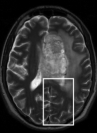

To examine the performance of our approach with brain MRI data when the assumptions of similarity between consecutive scans is not valid, we used retrospectively acquired data of a patient with GBM. The patient was scanned twice within an interval of five months, and exhibited changes between scans that occupy more than 50% of the brain region. We used T2-weighted FSE sequence (matrix: res = , 36 slices with thickness and no gap, TR/TE=, echo-train length=, flip angle=). We registered the follow-up scan to the baseline scan and examined the results of LACS-MRI (), CS-MRI and TCS-MRI with acceleration factors of 4, 6.4, and 10.6.

Table 3 shows the SNR values for different reconstructions and Figure 6 shows reconstruction results visually, at acceleration factor of 4 (25% of the k-space). In this case, there are major changes between the baseline and the follow-up scans due to therapy response. As a result, TCS-MRI exhibits poor performance in the vicinity of the changing tumor, since it is partially based on similarity between the consecutive scans, an assumption which is not valid in this case.

LACS-MRI, however, convergences to a result which is similar to CS-MRI. This is obtained thanks to the adaptive sampling and the weighting mechanism embedded in LACS-MRI, which reduces the weight given to the similarity to prior scan in the reconstruction process, if such a similarity does not exist.